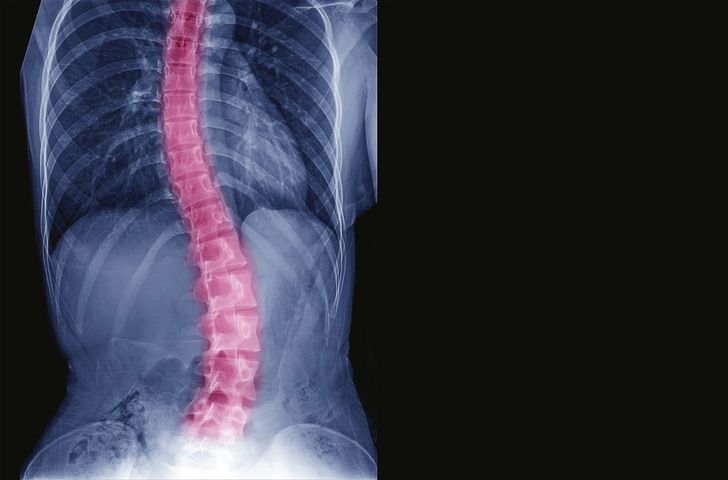

3. Abnormal spine curvatures

Image Credit: ChooChin/iStock.